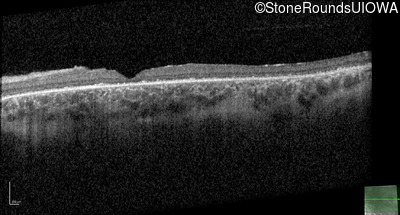

Optical Coherence Tomography - Left - 20/100 -2 sc

Exemplar / OCT Stack

OCT Stack